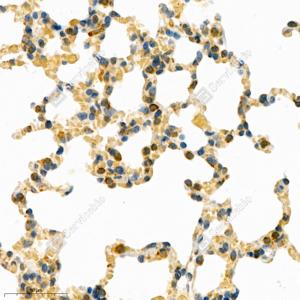

IHC检测PDIA6蛋白(货号 GB111171). 样品: 小鼠肺, 4%多聚甲醛 (货号G1101) 固定12-24小时. 抗原修复: 柠檬酸抗原修复液(干粉, pH 6.0) (G1201), 98℃, 20分钟. —抗: 1: 2000稀释, 4℃ 孵育过夜. 二抗: HRP标记山羊抗兔IgG (H+L) (货号GB23303), 1: 200稀释, 室温孵育1小时. |